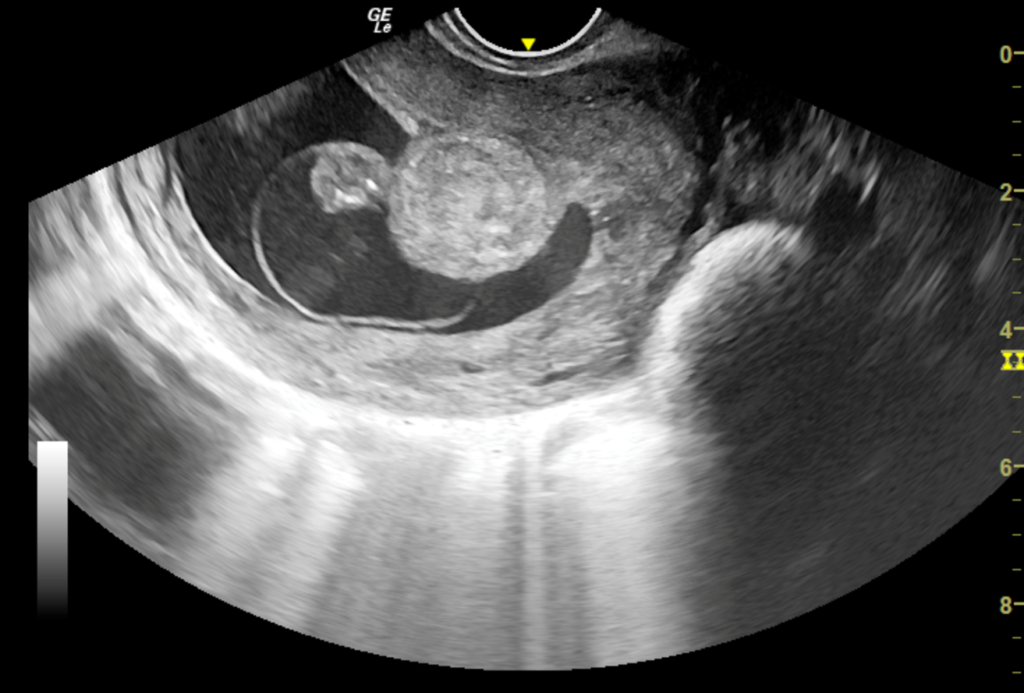

We report a case of a 24-year-old lady who was unable to conceive for a period of 8 years. Infertility workup was negative. In 2018, she conceived, however cardiac activity was not demonstrated in the fetus and eventually medical abortion was performed. Transvaginal sonography was performed for the same at a private center which did not pick up any uterine structural abnormality. In 2021, the patient presented to our emergency department with a 14-week gestation pregnancy with complaints of bleeding per vaginum for 2 days. Antenatal transvaginal ultrasound was performed for confirmation and viability of an intrauterine pregnancy. An intrauterine gestational sac with crown rump length corresponding to 8 weeks 5 days and absent cardiac activity was seen suggesting the diagnosis of missed abortion (Figure 1). Surrounding the gestational sac was fluid with internal echoes suggesting failure of implantation (Figure 2). A well-defined uniformly echogenic pedunculated lesion was seen in the endometrial cavity (Figure 3). As it was traced towards the point of its origin, a focally hypoechoic region was demonstrated interrupting the hyperechoic endometrial lining (Figure 4), classically described as the ‘interrupted mucosa sign’ [2]. On colour doppler image, a single vascular pedicle was demonstrated (Figure 5), known as the ‘pedicle artery sign’ [3]. Based on these classical features the diagnosis of an endometrial polyp was made. It was seen to abut the gestational sac suggesting mechanical hindrance to growth of the embryo (Figure 6). On real time imaging, the endometrial polyp was seen prolapsing from towards the uterine fundus to the lower uterine segment (Figure 7). For better characterization of the endometrial polyp, it has been recommended to distend the uterine cavity with saline (also known as saline infusion sonohysterography) [4,5], however in our case it was unwarranted because the gestational sac and fluid naturally distended the uterine cavity and helped in optimum visualization (Figure 4,6). Figure 8 depicts another case of an endometrial polyp showing a non-gravid uterus with an echogenic lesion in the endometrial cavity showing the classical interrupted mucosa sign (Figure 8A) and the feeding artery sign (Figure 8B).

Figure 3: Transvaginal sonography A) Sagittal section B) Axial section show a well defined, well contoured, homogenously hyperechoic lesion in the endometrial cavity with a stalk suggestive of endometrial polyp.

Figure 6: Axial section of transvaginal sonography depicting the mechanical hindrance to implantation and growth of fetus by the well defined polypoidal lesion. Also note the natural distension of endometrial cavity by fluid in gestational sac and endometrial cavity beautifully delineating the polyp margins thus obviating the need for saline infusion in this case.